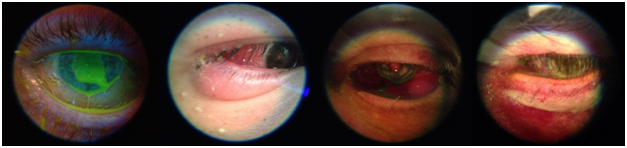

Figure 3. External images taken with the JEDMED Horus Scope

The initial exposure to the Welch-Allyn was useful but there were distinct limitations.It was adequate in training students on how to use an ophthalmoscope, however its utility was limited by the resolution of the camera. The field of vision oftentimes limited the visibility of the retina, and the image was too pixelated in the key principle locations (Figure 2). It did prove useful as an anterior segment device looking for small features in the cornea, anterior chamber, or conjunctiva (Figure 4). It was also difficult to operate the handheld - trying to stabilize the instrument while obtaining clear focus for capturing the image. It has great potential, however a much higher resolution is needed in order for it to become more acceptable.

Figure 4. External images taken with the Welch-Allyn Panoptic 11820